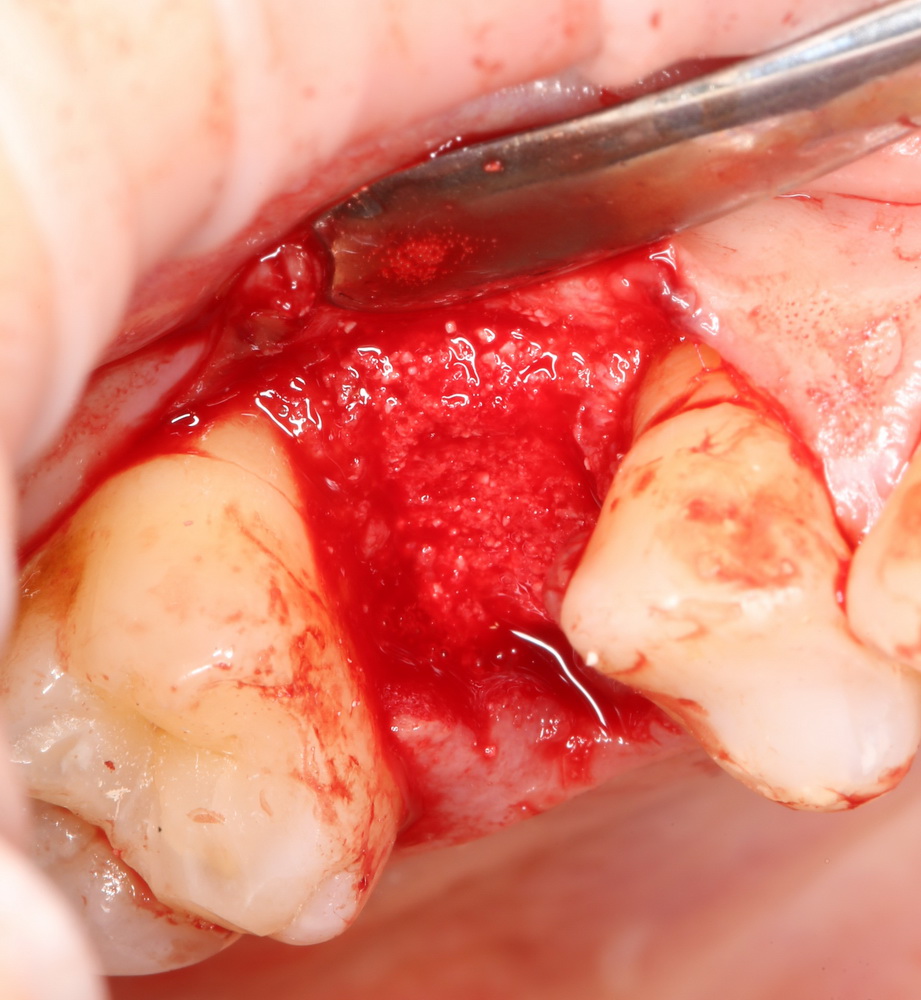

Вариант #1: Использование слизистотканного или соединительнотканного лоскута:

И все бы хорошо, но этот самый соединительнотканный лоскут нужно где-то взять. А это требует донорского участка и, следовательно, увеличивает травматичность и нашей операции, совершенно не добавляя комфорта в послеоперационном периоде. Зато можно сэкономить на материалах!)

Вариант #2: Использование коллагеновых матриц.

По сути, коллагеновая матрица в данном случае играет ту же роль, что и лоскут. При этом, нам не требуется где-то этот самый лоскут вырезать, не говоря уже о том, что адаптация и фиксация матрицы намного проще, чем даже самого тонкого соединительнотканного аутотрансплантата.

В своей практике я использую Geistlich Mucograft Seal, разработанный и предназначенный специально для аугментации лунок зубов. Это коллагеновая матрица, нарезанная кружочками 8 мм в диаметре:

В этом случае мы используем Mucograft Seal как наименее травматичный и наиболее простой способ герметизации лунки:

Матрица подшивается узловыми швами к краям лунки, таким образом достигается ее герметичность:

И вот что важно про швы. Любые другие способы подшивания что матрицы, что десневого лоскута, например П-образные или Х-образные швы, во-первых, не обеспечивают нужной герметичности, а во вторых создают излишнее натяжение краев слизистой оболочки, что приводит их деградации и стимулирует атрофию тканей. Так что лучше потратить побольше времени и зашить лунку так, как надо, чем потом переживать за результат операции.